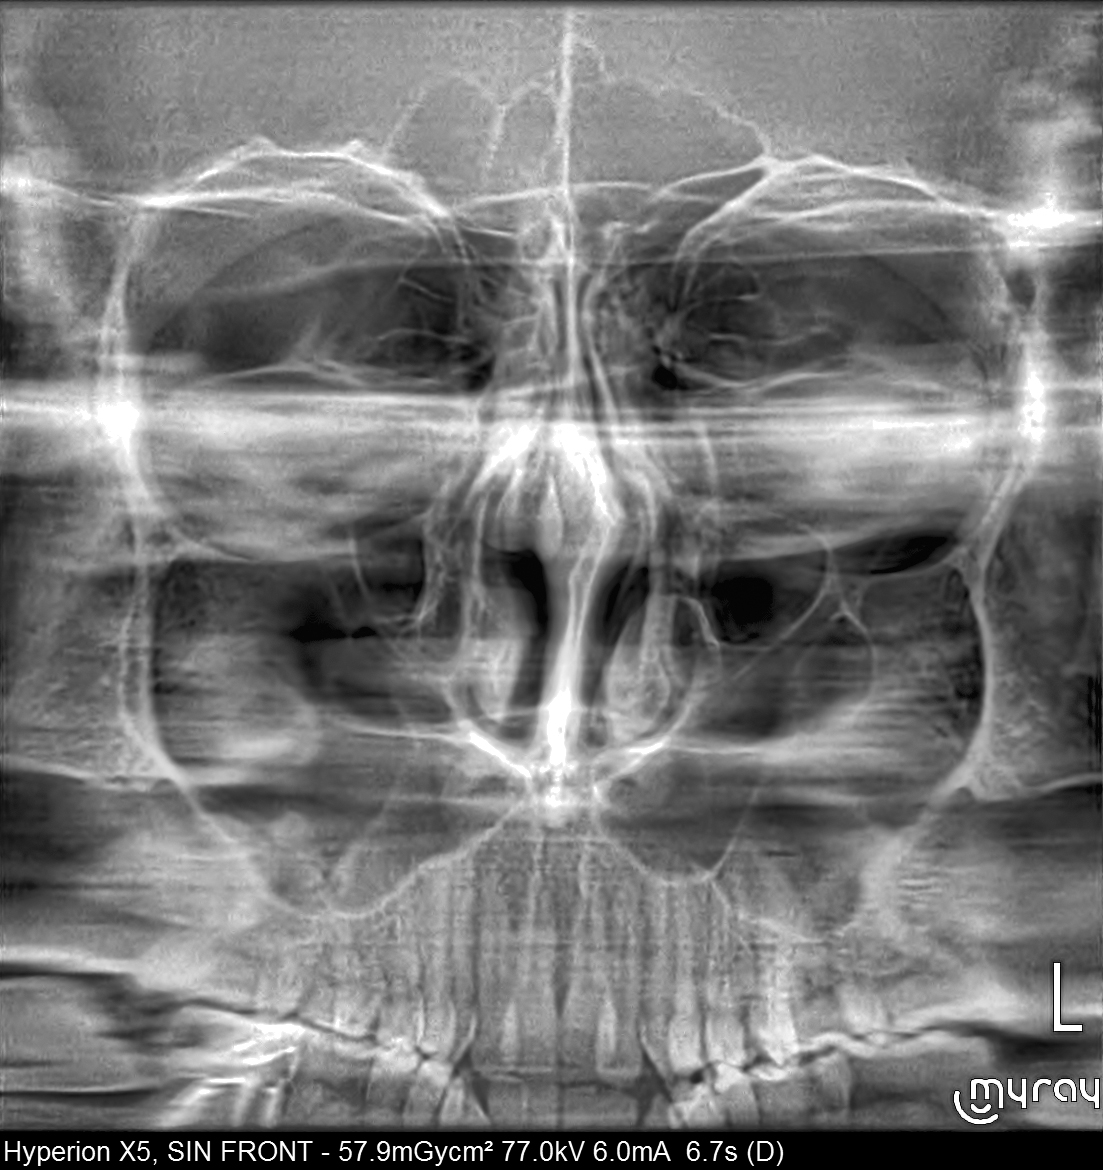

• SAĞ ve SOL Lateral Projeksiyonlar • Frontal projeksiyon

Tek bir taramada sinüsler bölgesinin görüntüsünü elde eder. Bu çekim modu, sinüs kaldırma ve hastalardaki morfolojik oranları değerlendirilmesine olanak sunmaktadır. Ayrıca hacimsel ölçüm, analiz dahil olmak üzere optimize edilmiş tedavi planlamaları olası hastalıkların dikkatle teşhis edilmesini sağlar.